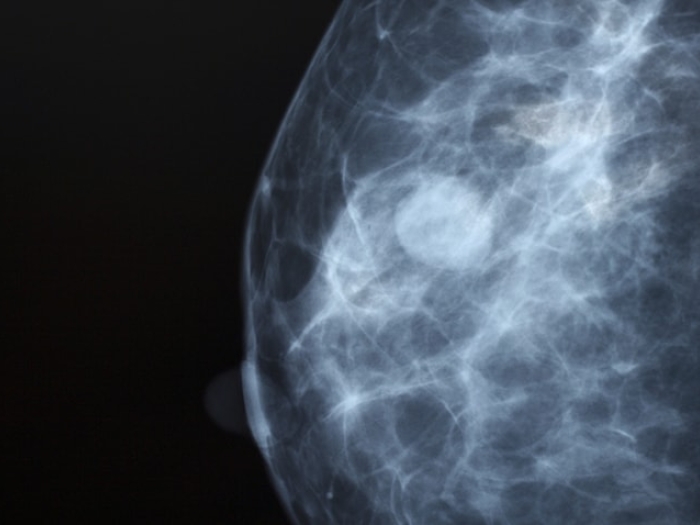

Ultrasound of dense breast tissue

What Women Should Know About Breast Density

Find out what it means to have dense breasts, including the four levels of breast density and why having dense breasts makes cancer detection more difficult.